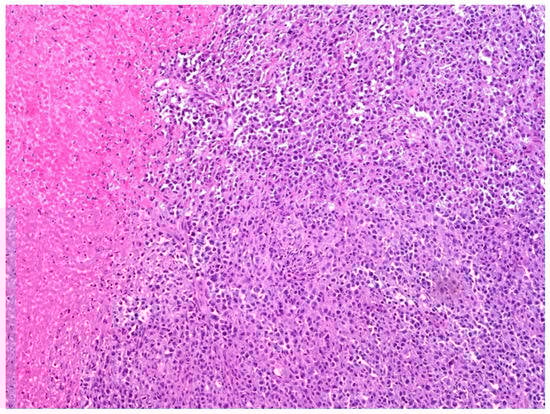

4. Diagnostic Approach for Primary Urinary Bladder Lymphoma

5. Histology, Immunophenotype, and Genetic Features of DLBCL, NOS